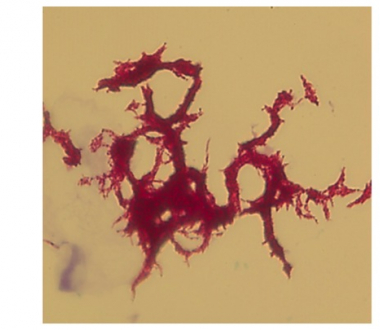

| April 14 | The isolate was also referred to the Wadsworth Center Mycobacteriology Laboratory by the NYC PHL for whole genome sequencing. DNA sequencing is performed to detect mutations in certain genes, indicating drug resistance. |

| April 25 | The Wadsworth Center Mycobacteriology Laboratory reported results indicating the presence of mutations in the following genes:  rpoB (rifampin),  katG (isoniazid),  inhA (isoniazid),  pncA (pyrazinamide), embB (ethambutol) and rpsL (streptomycin). The tests confirm the drug susceptibility findings of the NYC PHL. In addition, a mutation in gyrA was detected, predicting resistance to fluoroquinolone, a major class of second line drugs for treatment of MDR strains. This was crucial information that allowed the treating physician to modify the ongoing drug regimen prior to the availability of results from conventional second line drug susceptibility testing. |